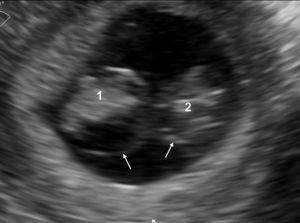

First trimester The ideal time to determine chorionicity is the first trimester. As early as 4–5 weeks postmenstrual weeks, by using transvaginal sonography, it is possible to recognize the chorionic sacs inside the uterine cavity within the tick deciduas. They appear as sonolucent round structures with a brightly echogenic rim. By simply counting the chorionic sacs it is possible to establish whether the pregnancy will be monochorionic, dichorionic, trichorionic and so on (Fig. 1).

The visualization of a single chorionic sac at 4–5 weeks, however, does not exclude the possibility of a monochorionic twin pregnancy. By the sixth postmenstrual week the yolk sac and the embryo can be visualized inside the chorionic sac and the definitive diagnosis of a single pregnancy or monochorionic twin pregnancy can be done. If a single chorionic sac is visualized containing two yolk sacs and two embryonic poles, then a monochorionic twin pregnancy can be diagnosed (Fig. 2).